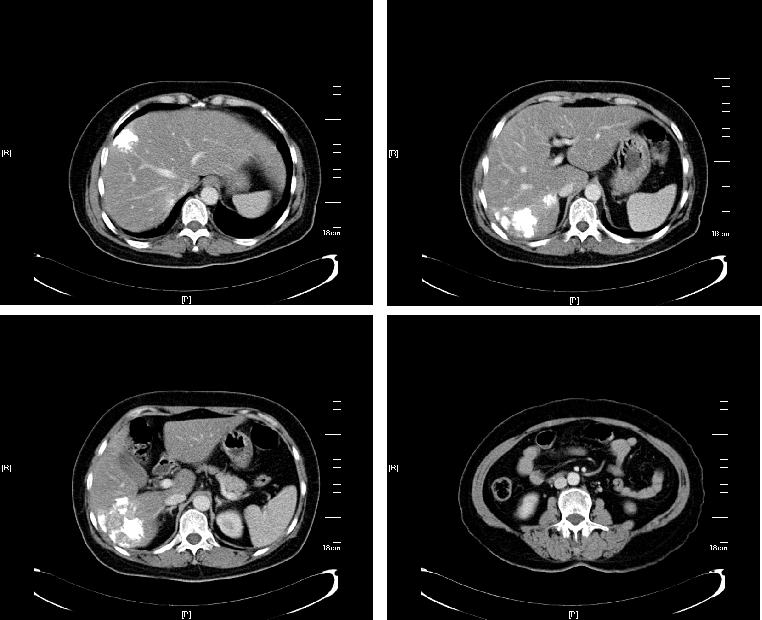

治疗后,原发灶及转移灶明显缩小,肿瘤标志物明显下降。

△治疗后

右肝转移灶明显缩小,左肝转移灶消失,残肝体积足够,意外达到成功转化,分期行原发灶及肝转移根治性切除手术,且原发灶和转移灶术后病理均达到pCR。术后继续完成围手术期化疗,并定期随访,现无瘤生存。